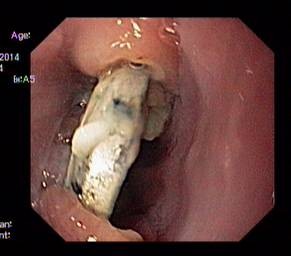

Cục pin tròn găm vào thành thực quản - ảnh Khánh Chi - Viên Nhi Trung ương

Tiến sĩ Phan Thị Hiền, Trưởng khoa Nội soi cùng ê-kíp nhanh chóng tiến hành nội soi và phát hiện tại đoạn thực quản trên có hình ảnh dị vật tròn găm vào 2 thành thực quản.

Các bác sĩ gắp ra được một cục pin hình tròn, đường kính 1,5 cm, đã hoen gỉ ở các cạnh. Thực quản cháu bé bị loét sâu, có giả mạc và rớm máu. Sau 24 giờ theo dõi, cháu bé đã hồi phục và được ra viện.

Các bác sĩ gắp ra được một cục pin hình tròn, đường kính 1,5 cm, đã hoen gỉ ở các cạnh. Thực quản của bé bị loét sâu, có giả mạc và rớm máu.